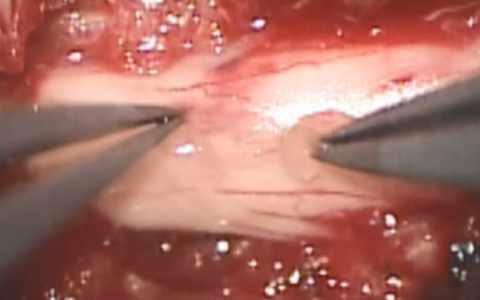

さらに、ラット脊髄髄膜瘤モデルを用いて羊水幹細胞シート移植による胎児手術の開発を目指した研究も開始しており、脊髄疾患の治療発展への貢献を目指し、研究を続けています。